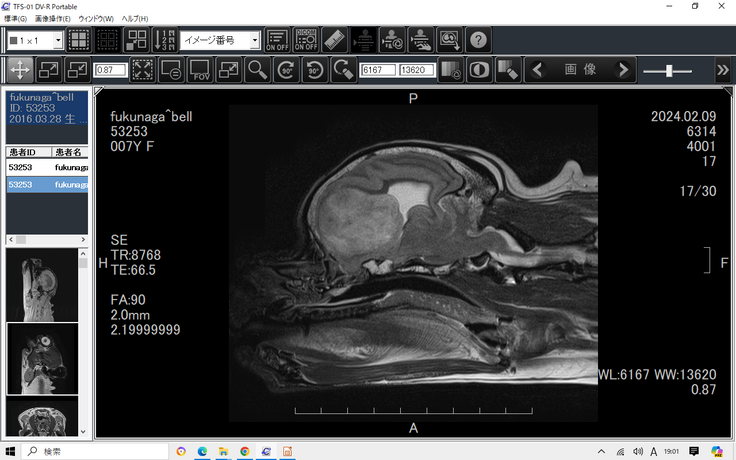

別な病気を疑われ、かかりつけ医はMRI・CTが必要と判断

検査は頭を固定する為に全身麻酔をかけます。

ワンコの全身麻酔にはリスクが伴いますが、検査に踏み切ります。

MRI・CT検査の結果、頭の半分程を埋める異物が見つかりました。

てんかん発作の本当の原因がこの異物に隠されていました。

病理組織診断の結果は希突起膠細胞腫。活発で悪性度の強い脳腫瘍

再発の可能性が高いため、早い段階での放射線治療が必要です。